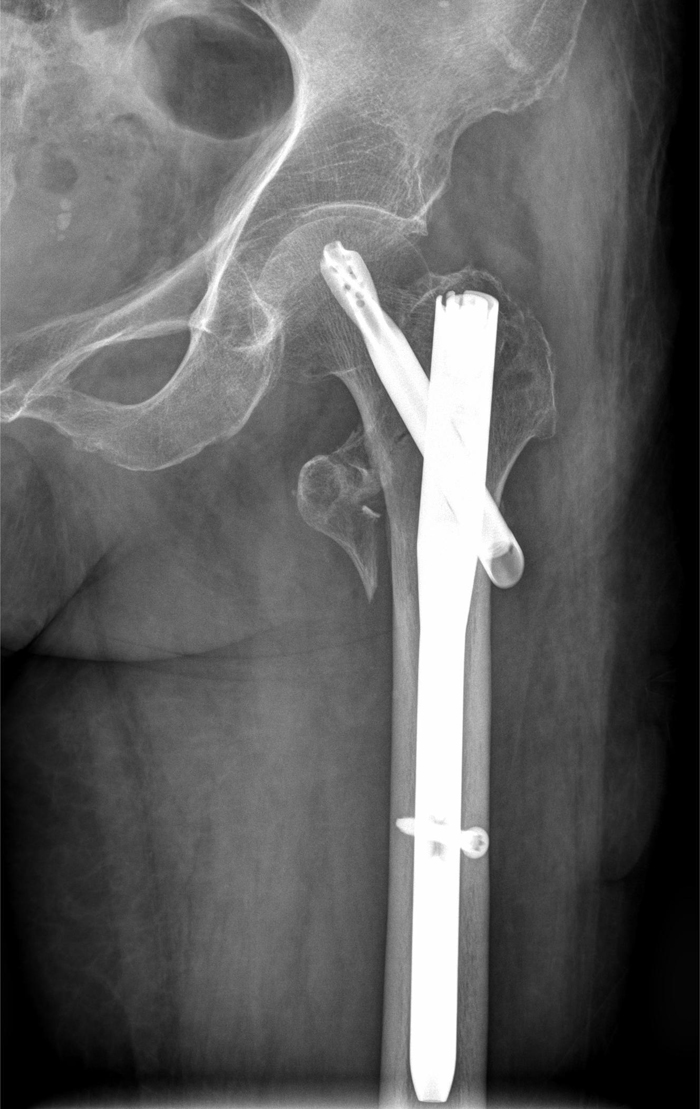

术后

近日,骨中间借助绿色通道又成功救治了一位98岁高龄髋部骨折患者。四月初,朱奶奶在家掉慎摔伤,当即感到左侧髋部苦楚悲伤难忍,无法起身行走,被家眷紧急送到潞河病院。急诊骨科大夫接诊后敏捷完美检查,明白诊断为左股骨转子间骨折,于是第一时光启动绿色通道收入骨中间创伤骨科病区。患者入院后,医疗部敏捷批示调剂,骨中间召集骨科、麻醉科、手术室、心内科、老年医学科科、内渗出科等多学科专家敏捷会诊,合营制订了详尽的术前检查与手术筹划。经由周全评估与检查,清除了手术禁忌后,朱奶奶于入院12小时内顺利进入手术室,由龙安华副主任医师、杨琦医师实施机械人帮助下左股骨转子间骨折微创髓内钉内固定术。凭借团队精深的技巧和丰富的经验,在骨科机械人精准帮助下手术用时仅40分钟,出血量少于50毫升,以最大年夜程度的微创方法顺利完成了手术。